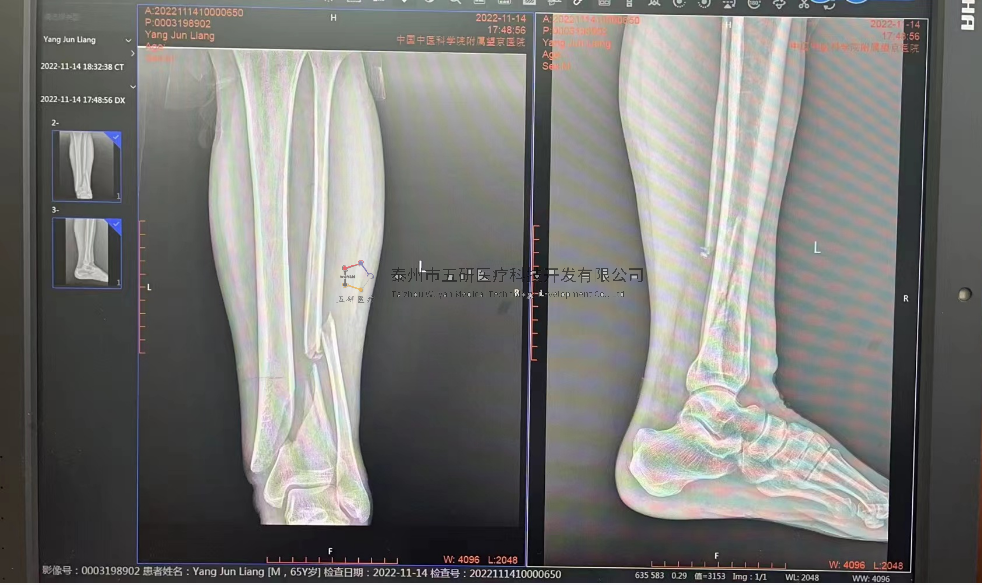

// 下肢骨折

【所屬科室】中國(guó)中醫(yī)科學(xué)院望京醫(yī)院創(chuàng)一科

【基本資料】患者,男,65歲

【患者情況】脛骨遠(yuǎn)端骨折伴腓骨骨折

【影像圖片—術(shù)前】

9.png